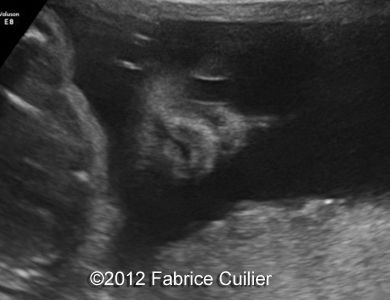

Image 2,3 : Coronal view of mouth and face at 28 weeks.

4a

4b